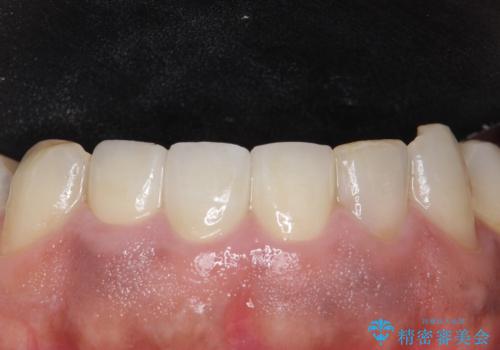

インプラントは希望されなかったため、左側は1番から7番のロングスパンブリッジによる補綴を行いました。

今回用いたオールセラミッククラウンは、ジルコニアフレームという白い素材の上にセラミックを盛っているため審美性が非常に高いのが特徴です。

またジルコニアは人工ダイヤモンドの材料にも使われているほど高い強度を持っており、そのためオールセラミッククラウンは審美性だけでなく、奥歯やブリッジの補綴も可能とするクラウンです。